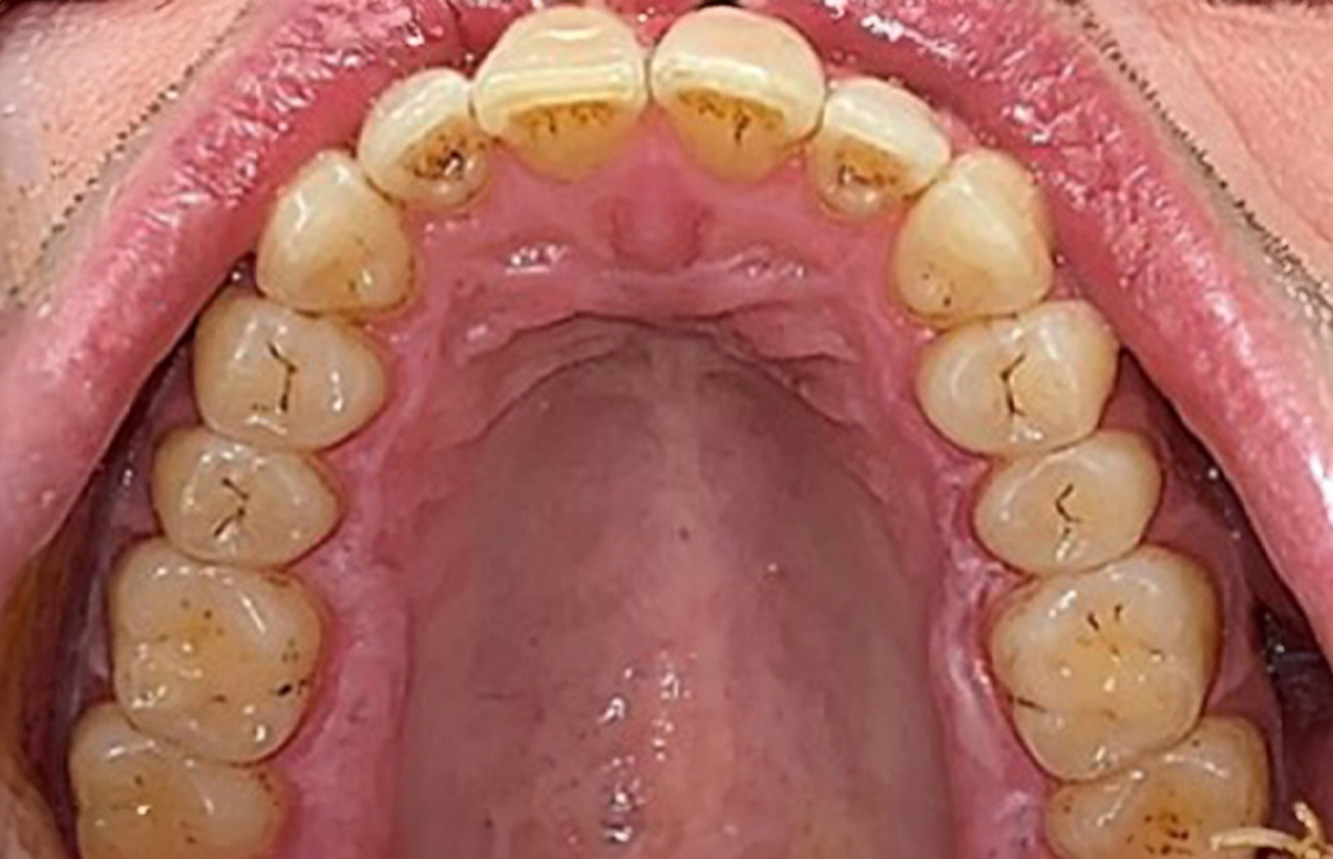

In the medical history, the 55-year-old patient states that he has no systemic disease and is not taking any medication. The patient’s lifestyle is similarly unremarkable. The patient has a few tooth restorations and two implants (2nd and 4th quadrants). On the basis of current findings, gingivitis is identified in an otherwise stable periodontal condition on the reduced periodontium (stage III, grade A). more

The healthy patient with pre-existing periodontal disease & peri-implantitis

The 68-year-old patient has no general health conditions and is not taking any medication that may be relevant to her oral health, and her lifestyle does not pose any particular risk. The patient has two dental implants (3rd quadrant, for five years) and a previous case of periodontal disease (stage IV, grade B periodontitis) with tooth loss. Currently the periodontal conditions are stable. However, periodontitis significantly increases the biological complications of implantations and there is a risk of implant loss (21). Four recommendations can be determined for the prophylaxis session. more